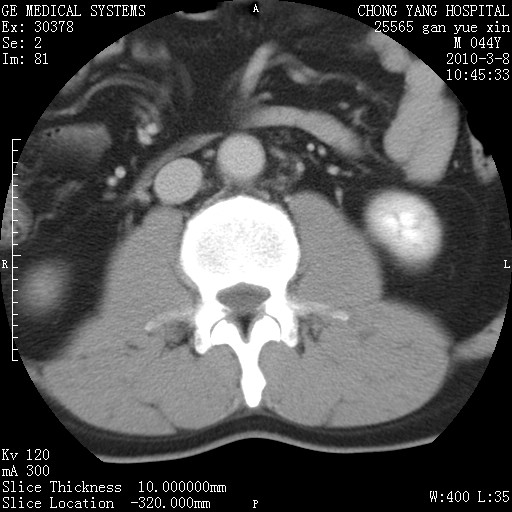

标题: CT24940:主动脉增强,典型病例。 [打印本页]

标题: CT24940:主动脉增强,典型病例。

夹层动脉瘤。

动脉夹层

夹层动脉瘤,典型

主动脉夹层。

动脉夹层的分型:

⒈debakey分型:根据主动脉夹层累及部位,分为三型:ⅰ型:原发破口位于升主动脉或主动脉弓部,夹层累及升主动脉、主动脉弓部、胸主动脉、腹主动脉大部或全部,少数可累及髂动脉。ⅱ型:原发破口位于升主动脉,夹层累及升主动脉,少数可累及部分主动脉弓。ⅲ型:原发破口位于左锁骨下动脉开口远端,根据夹层累及范围又分为ⅲa,ⅲb。ⅲa型:夹层累及胸主动脉。ⅲb型:夹层累及升主动脉、腹主动脉大部或全部。少数可累及髂动脉。

⒉stanford分型:a型:夹层累及升主动脉,无论远端范围如何。b型:夹层累及左锁骨下动脉开口以远的降主动脉。

夹层动脉瘤,少量胸水

夹层动脉瘤;左侧少量胸腔积液。